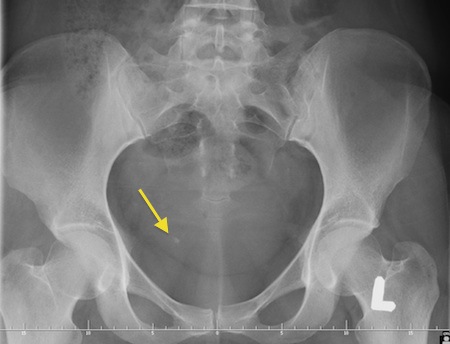

Ustalenie lokalizacji złogu w moczowodzie czasami bywa trudne w warunkach ambulatoryjnych. W przypadku podmiedniczkowego i śródściennego odcinka moczowodu czasami udaje się uwidocznić złóg w czasie USG jamy brzusznej. Złogi uwapnione w większości przypadków widoczne są na zdjęciu przeglądowym jamy brzusznej. Aby dokładnie uwidocznić kamień i ustalić czy cienie mogące być uwapnionymi złogami na zdjęciu zlokalizowane są w moczowdzie należy wykonać urografię lub tomografię komputerową. Czasami konieczne jest ustalenie lokalizacji złogu wykorzystując pielografię zstępującą - u pacjentów z przetoką nerkową - nefrostomią lub pielografię wstępującą.

Fot. Zdjęcia przeglądowe jamy brzusznej pacjentów z kamicą moczowodową. strzałkami zaznaczono złogi w moczowodach.